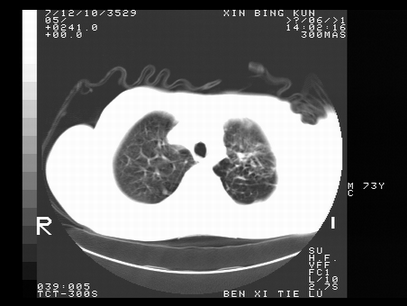

标题: CT10820:男,73岁,病史肺TB,现病史肺炎,直肠CA术后 [打印本页]

标题: CT10820:男,73岁,病史肺TB,现病史肺炎,直肠CA术后

1.两肺结核.2.两肺多发转移瘤.3右侧少量胸腔积液4.主动脉钙化.

双肺多发结节及条片状致密影,右侧少量胸腔积液。临床:直肠ca术后,肺tb病史。综合考虑:1 双肺转移!2 继发性肺结核合并感染!

此人病史较复杂,原有肺结核,直肠癌术后。肺部病灶形态亦呈多形性。因此,不可仅以一种病来解释肺部的病变。双肺多发的类圆形结节灶,结合病史还是首先考虑转移瘤,而双肺其余病灶还需结合化验室检查,结核或肺部感染在无其它检查资料的情况下不好排除。还是那句话----放射科医生不是开照像馆的,我们也是医生,看片一定要多结合临床及其它检查资料。要当一名合格的放射科医生,并不比当一名临床医生容易,我们可别把自已不当医生看。

两肺多发结节影,并见滋养动脉与其相连,考虑 两肺转移. 右侧胸腔积液考虑胸膜转移.

左肺上叶下叶背段,右肺中下叶见多发斑片状、条索状高密度影,兵变周围小结节影形成“树芽”样改变。 左肺上叶舌段近前胸壁处及右肺中叶内侧段见结节影。右侧胸膜腔内见液体密度区。纵隔内未见明确增大淋巴结。考虑左肺上叶舌段近前胸壁处及右肺中叶转移瘤可能性大。两肺继发型肺结核。右侧胸腔积液。

还有心包少量积液。